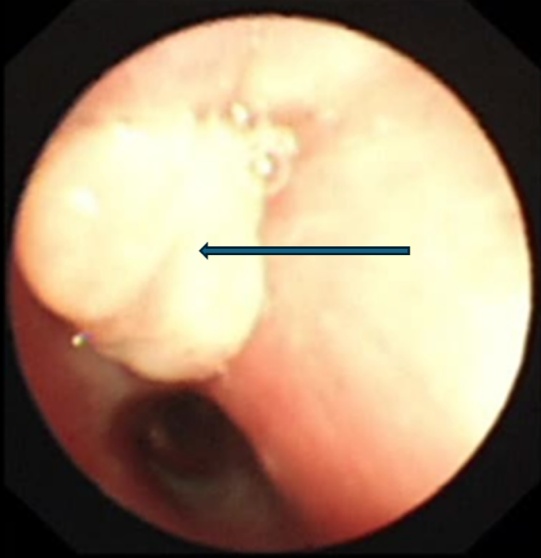

支气管镜下的景象触目惊心:乐乐右主支气管管腔内满是脓性分泌物,且增生的肉芽组织堵塞了右上叶支气管开口。在更深处,一个看似尖锐异物死死堵住了右中间支气管管腔。

支气管镜检查显示右上叶支气管肉芽增生,完全堵塞开口